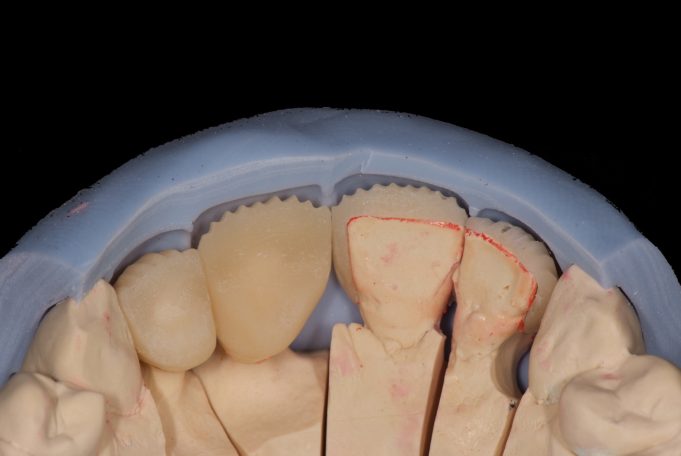

Metallfreie Frontzahnkronen mit individueller keramischer Verblendung.

Virtuelle Planung mit Vorab-Provisorium aus dem Labor.

Frontzahnkronen Oberkiefer neu zur Verbesserung der Ästhetik.